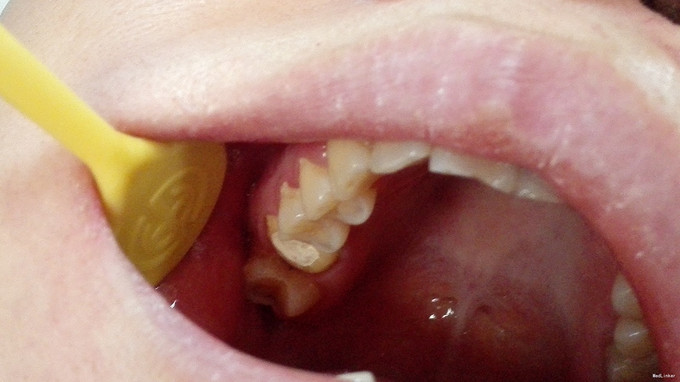

检查:16牙合面暂封完好,咬合紧,牙合龈距离<5mm,叩痛(-),牙体无松动,牙龈未见异常 X线示:16已根治,根充良好,根充物恰到根尖孔,根尖及牙周未见异常

诊断:16牙体缺损 治疗计划:16嵌体冠修复 治疗:1.取局部印模,制备髓腔固位形,预备牙体,取模,比色:A3, 寄送加工厂,制备临时冠,试戴,调合,磨光,粘固临时冠 2.主诉:戴牙 检查:16临时冠完好,叩痛(—),牙体无松动,牙龈未见异常 处置:戴入16全瓷嵌体冠,调节使就位顺利,与基牙密贴,冠边缘伸张合适,邻接恢复良好,调牙合,抛光,患者满意,U200粘固,嘱须知